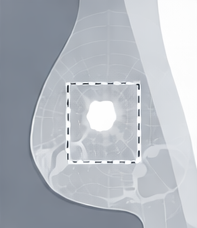

Wide Local Excision / Lumpectomy

Breast conserving surgery to remove cancer and preserve remaining breast tissue.